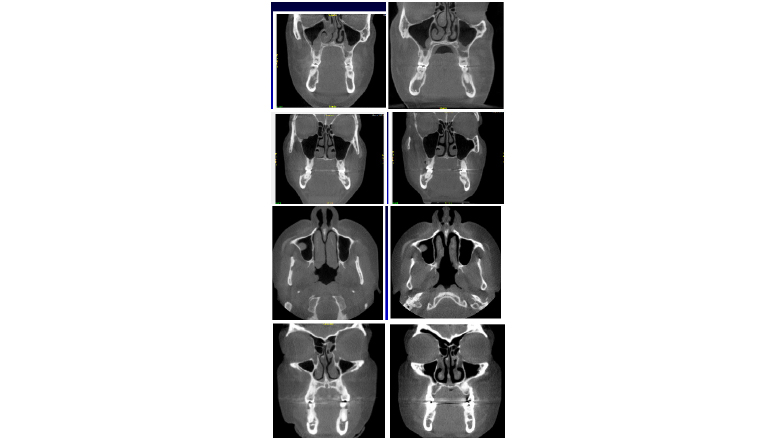

Figura 2. El Homeoblock™, un aparato ortodóntico removible de expansión palatina y maxilar, abre la respiración nasal: el lado izquierdo antes y el derecho después.

Todos estos pacientes muestran una mejoría en la respiración nasal, una reducción de la inflamación y una menor hinchazón de los cornetes.

El aparato Homeoblock aumenta el volumen de la parte media de la cara, incrementa el volumen nasal, mejora la coherencia del sistema nervioso autónomo y reduce la inflamación.